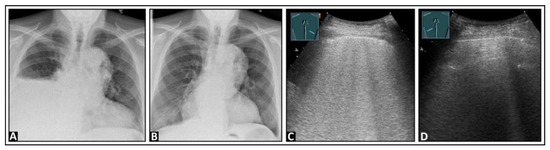

3. Underlying Pathology in Artifacts

4. Pulmonary Edema and Acute Respiratory Distress Syndrome